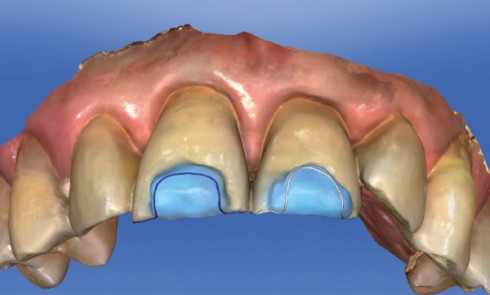

Article réservé à nos abonnés Protocole de réalisation par cfao directe de facettes palatines avec crochet vestibulaire

INDICATION GÉNÉRALE DES FACETTES PALATINES L’indication de facette palatine est motivée par la présence d’une perte de substance intéressant une...